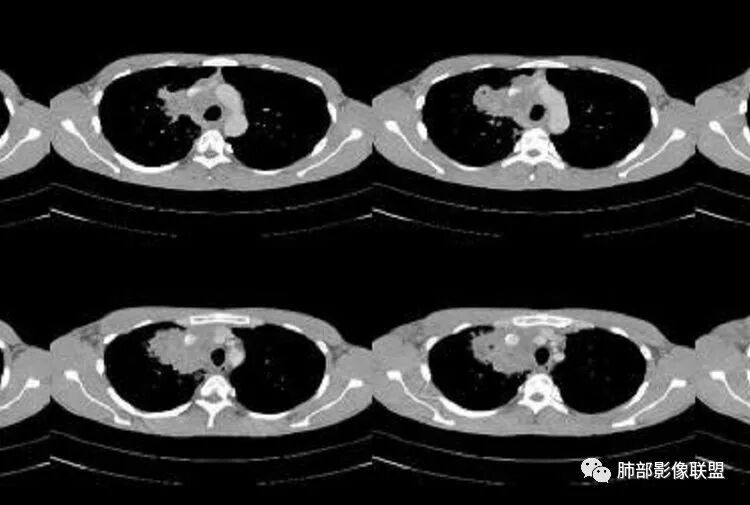

有栽赃吗?

这种属于宽基底与胸膜相连,附近胸膜增厚

栽赃是局部外侵犯

这里没有栽赃

如下图病例红色箭头的是典型栽赃:

南边 :

而该病例栽赃不明显,与增厚的胸膜分界比较清晰

3、病灶密度不均,可见钙化点,未显示空洞或液化。边缘收缩,U型凹陷、桃尖征、细长毛刺以及较长棘状突起。宽基底与胸膜相连,邻近胸膜广泛性增厚(未见栽赃侵入)。可见卫星病灶,周围的磨玻璃影比较松散,炎性病变征象多,符合结核的CT表现。

4、部分区域膨隆,未见支气管截断,肺门纵隔未见肿大淋巴结等,恶性征象少。